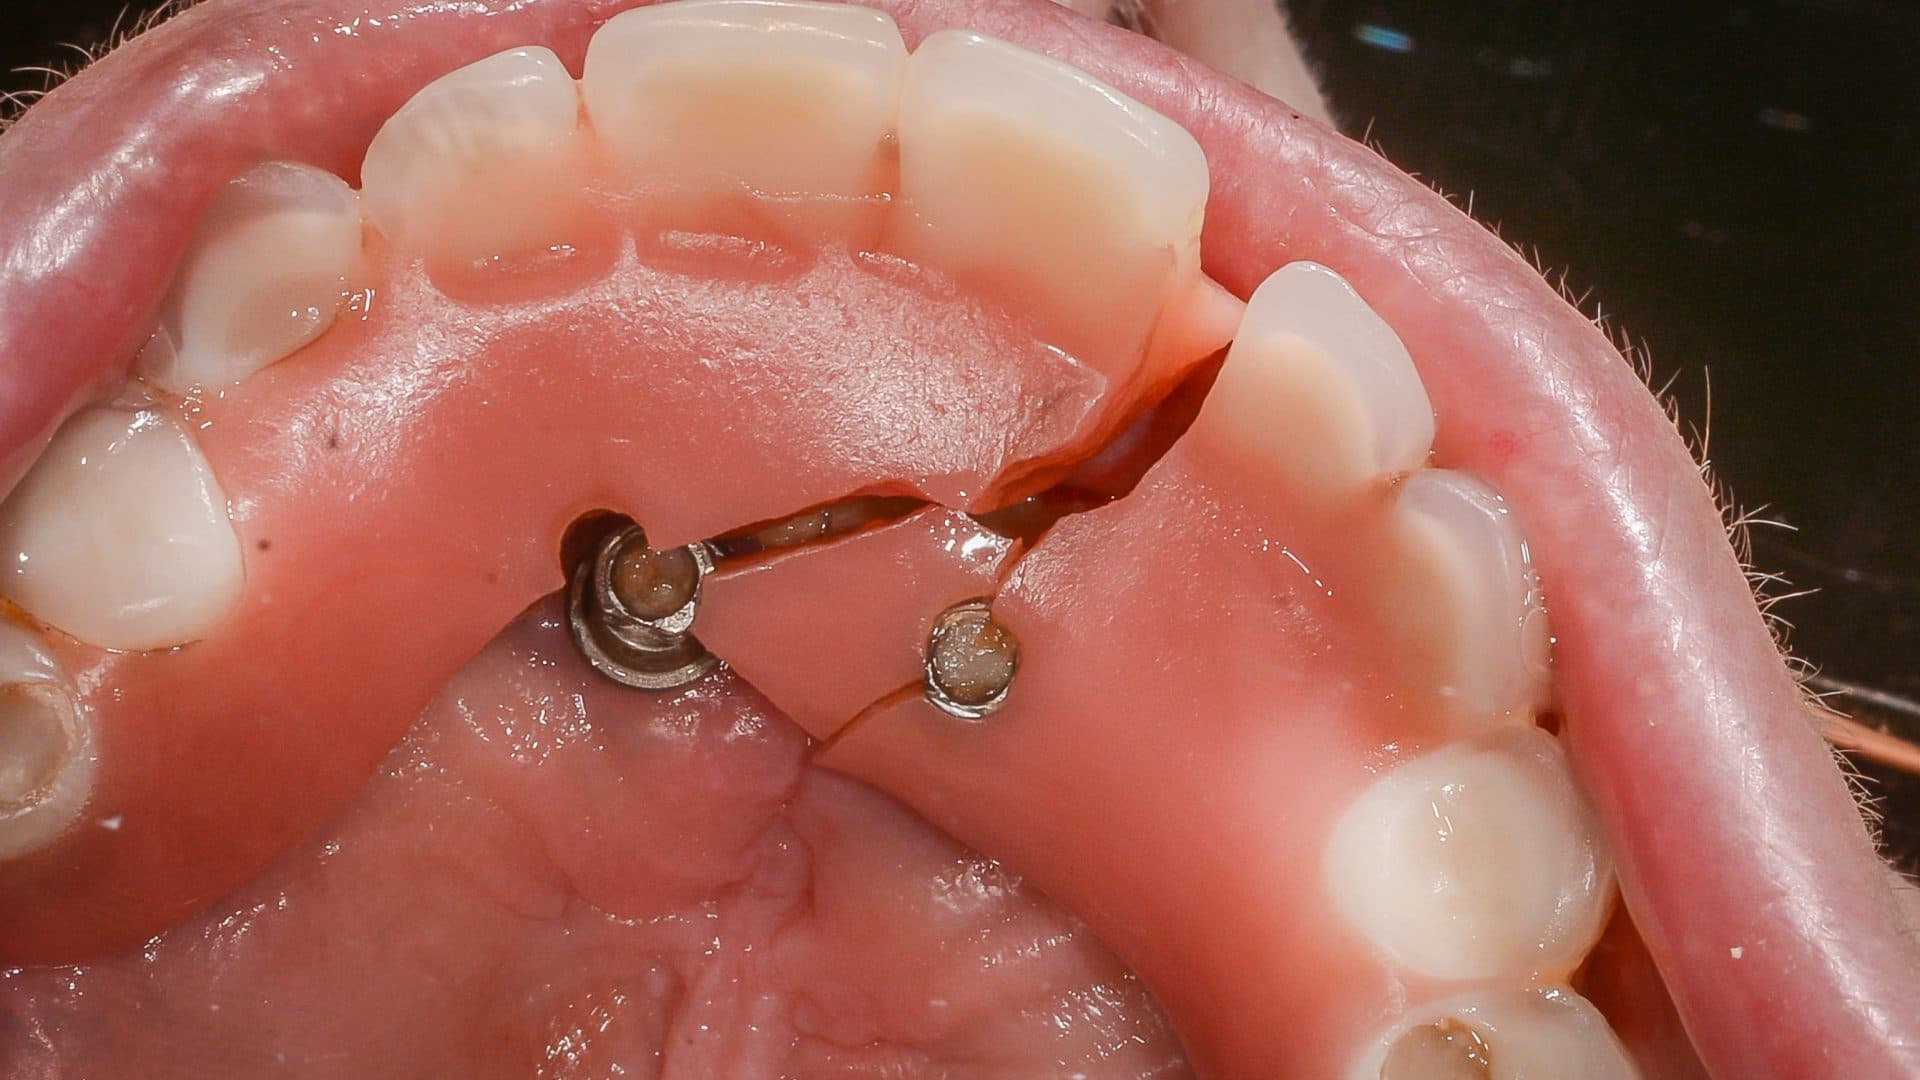

Here is a graphical overview of the ideal situation compared to poor standards with All-on-4 Plus® dental implants.

Ideal Situation

Poor Standards